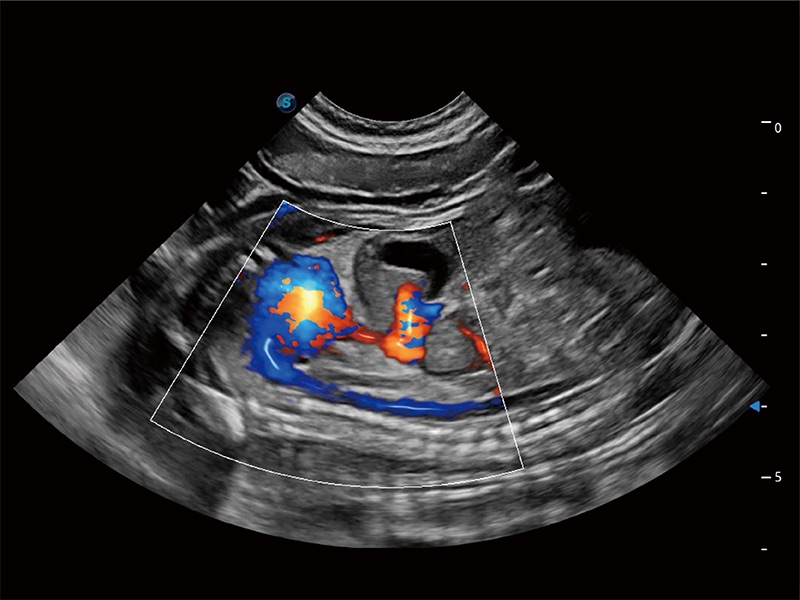

在传统二维血流成像的基础上,呈现血流的立体感,具有动感的生命力之美。即便是微小的血管也能轻松应对,提高了血流的视觉敏感性。